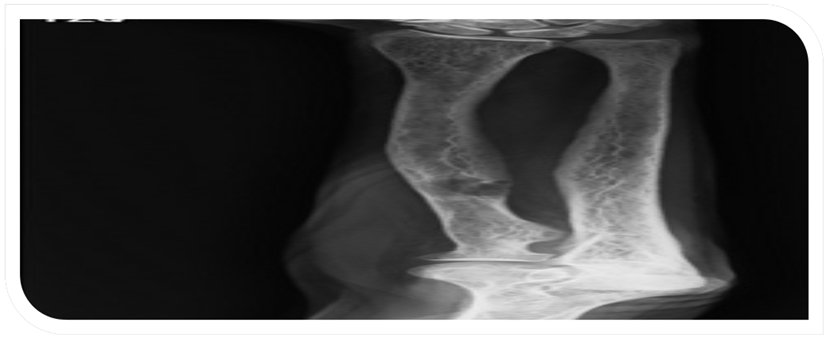

Mujer de 71 años, delgada, con buena funcionalidad previa (Barthel 100/100) y antecedente de osteoporosis, presentó dolor súbito y limitación para la marcha por fractura subcervical de fémur izquierdo (Figura 1), se programó osteosíntesis considerando fractura por fragilidad. Al ampliar estudios se documentó síndrome constitucional de dos meses de evolución, nefrolitiasis, anemia microcítica y lesiones osteolíticas generalizadas (Figura 2). Se consideraron neoplasias de células plasmáticas como el mieloma múltiple y metástasis óseas de neoplasias ocultas, como las ginecológicas. Estudios tomográficos mostraron nódulo pulmonar inespecífico con derrame pleural escaso y nódulo tiroideo de 4 cm (Figura 3), ecografía de tiroides indicó nódulo de alto riesgo y biopsia por trucut reportó adenoma folicular oncocítico.

Radiografía de huesos largos. Lesión osteolítica en radio, sugestiva de metástasis óseas vs. tumor pardo.

Figura 2: Radiografía de huesos largos. Lesión osteolítica en radio, sugestiva de metástasis óseas vs. tumor pardo.

Fuente: los autores.